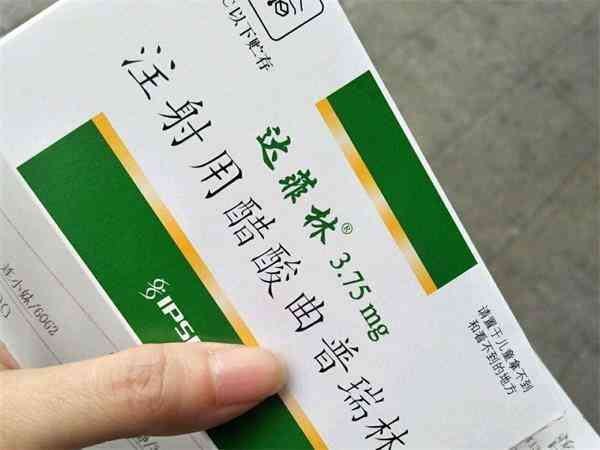

降调14天和28天的区别一览,注射药物和适用人群均有差异

在试管婴儿治疗过程中,许多患者通常会用到试管长方案和试管超长方案,他们的降调时间也是不同的。降调的目的在于调整女性卵巢功能,一般会使用降调药物进行注射,争取同一时间获得多枚优质成熟的卵泡。在试管中降调节打14天与28的区别主要有一点就是打针的时间长短不一样。14针的是短效要打14天,28天的也是短效但是需要打28天。

浅谈打达菲林降调针的位置,到底是哪个部位一看便知

达菲林降调针在试管婴儿的临床应用上是比较常见的,它的注射方式是肌肉注射,大部分女性患者在做试管婴儿的时候都是采用的是臀大肌注射,但也有采用三角肌和肱二头肌进行注射的,其中针对三角肌的具体肌肉注射部分是整块肌肉都可能进行的,但最好是按照医生嘱咐的部分进行注射,防止出现不良反应,建议这位女性患者最好是直接联系医生进行详细的询问和了解。